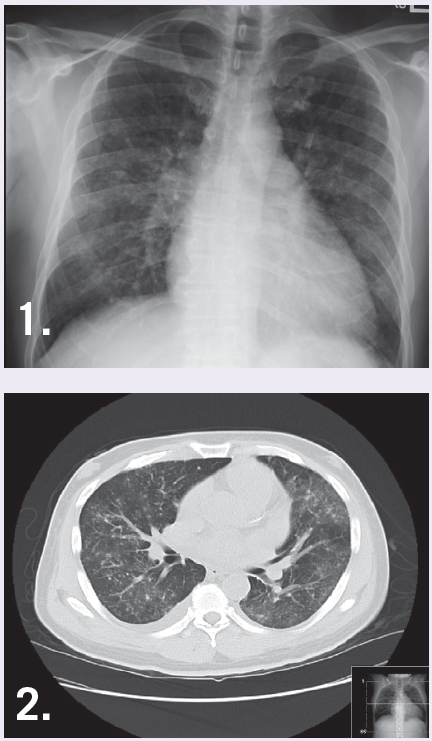

Laboratory tests. Initial laboratory examination revealed mild normocytic normochromic anemia, normal electrolytes, BUN of 62 mg/dL, creatinine of 2.5 mg/dL, pro-BNP of 8307 pg/mL, and an arterial blood gas showed hypoxemia. An EKG showed no new ischemic changes and a chest x-ray showed bilateral interstitial infiltrates, not entirely consistent with pulmonary congestion (Figure 1). On day 2, he developed a fever of 102.8 °F. A chest CT without contrast revealed micro calcifications and patchy ground glass opacity throughout the lungs (Figure 2). Varicella-zoster virus antibody was positive.